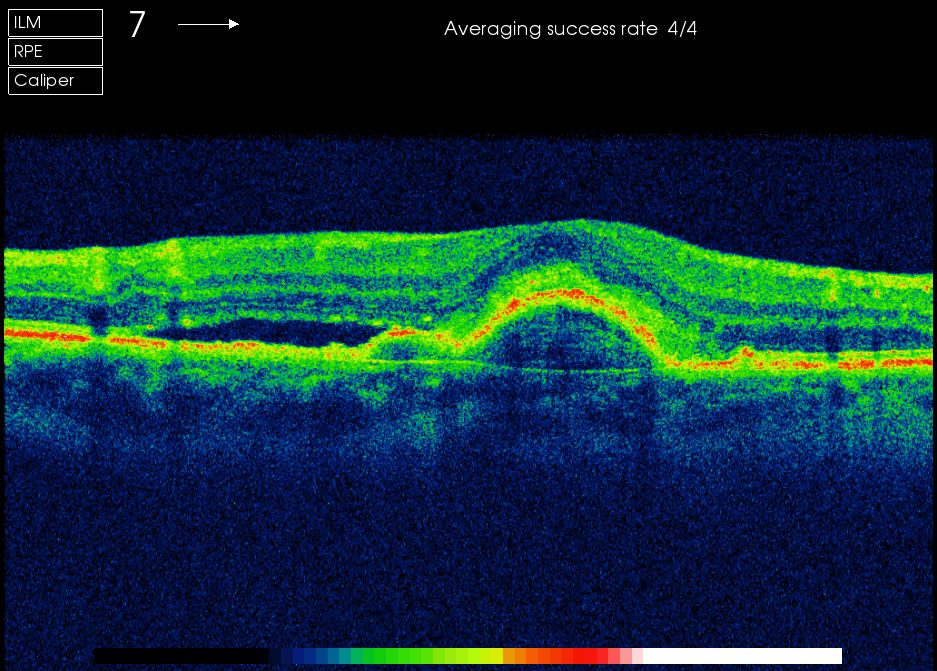

Feuchte AMD: Direkt unter der Fovea ist das Pigmentepithel aufgeworfen, links davon ist Flüssigkeit unter der Netzhaut ausgetreten.

Optische Cohärenztomographie OCT

Das OCT ist inzwischen der Goldstandard in der Beurteilung von Makulaerkrankungen. Sowohl die Diagnose als auch die Verlaufsbeurteilung und nicht zuletzt der Behandlungserfolg der Therapie hängen maßgeblich davon ab.

Auch die Dicke der Nervenfaserschicht im Bereich des Sehnerven kann hochauflösend dargestellt und vermessen werden, ein wichtiges diagnostisches Maß bei Sehnerverkankungen.